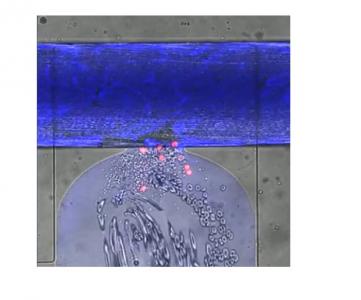

Le dispositif est le tout premier à reproduire tous les aspects des lésions des micro-vaisseaux observées dans les plaies et les lésions, de la perte de sang liée à un traumatisme, de la coagulation, et de la réparation de l’enveloppe des vaisseaux sanguins. Le système se compose ainsi d'une couche de cellules endothéliales humaines, qui tapissent les vaisseaux sanguins, cultivées au-dessus d'une valve pneumatique. La plaie est créée en activant une valve pneumatique, ouvrant une trappe permettant au sang humain de circuler à travers la plaie, qui fait environ 130 micromètres de diamètre.

Une vidéo présente ce dispositif avec la plupart des cellules sanguines en gris, les plaquettes sous forme de tâches plus petites et les globules blancs en rouge. Une « colle » extracellulaire, en vert apparaît au sommet de la plaie, c'est la fibrine. Le processus de coagulation observé à l’aide du dispositif prend environ 8 minutes.